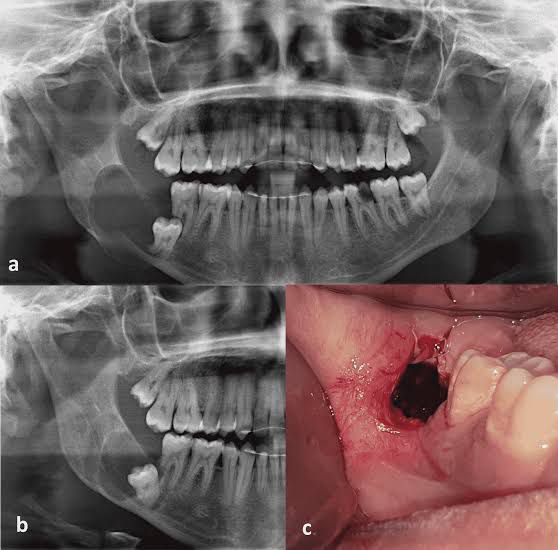

Dentigerous cysts are a common type of odontogenic cysts. An odontogenic cyst is a fluid-filled sac that develops in the jaw bone over a tooth that hasn't erupted yet. The cysts, in most cases, affect the molars or canines, and they're second in prevalence after periapical cysts.